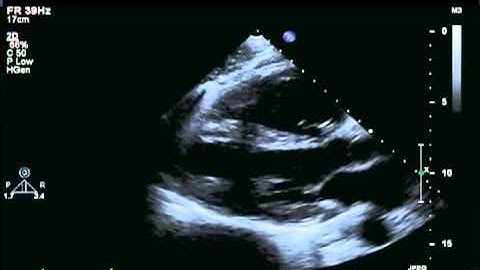

078 Basic View TEE KAMC